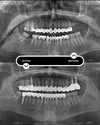

Implant tedavisi